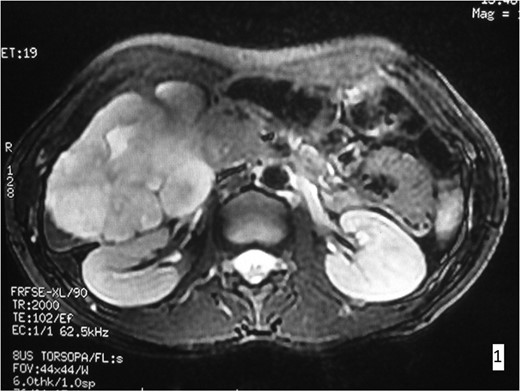

A 38-year-old woman was referred to the surgical out-patient Department of our Center presenting abdominal discomfort and recurrent episodes of acute abdominal pain during the previous 6 months. Her clinical and surgical history were free, and the patient did not mention any other symptoms. Physical examination only revealed tenderness during palpation of the right upper abdominal quadrant. Laboratory blood examination showed results within normal limits. CT-scan and MRI were ordered, in order to further investigate this condition. These imaging controls revealed the presence of a giant hemangioma (~9.6 cm in diameter), involving segments VI and VII of the liver (Figs 1 and 2). Therefore, in this symptomatic patient, considering the location, size and possible future complications of the lesion, a right segmental hepatectomy was decided.

MRI imaging. In the right hepatic lobe a lesion of 9.6 × 8.9 × 7.9 cm3 is observed, hyperdense in T2W presenting contrast enhancement.